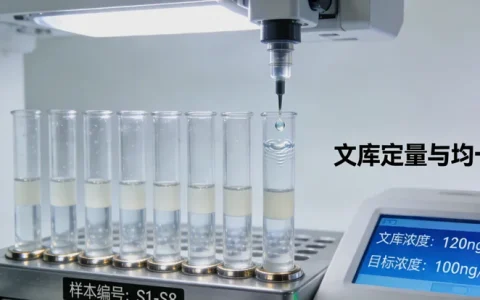

- 检测技术:优先选择采用NGS等高通量测序技术的机构,确保检测准确性和全面性。

- 服务流程:了解样本采集、报告解读等全流程服务,选择提供专业遗传咨询的机构。